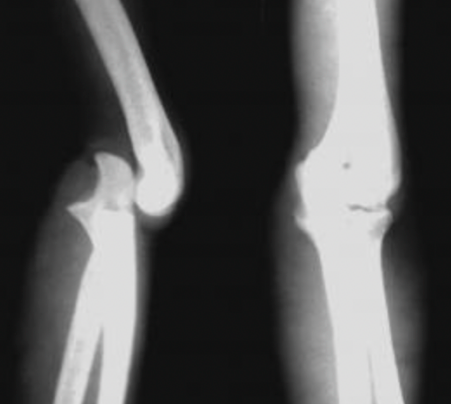

儿童肘关节脱位 儿童陈旧性肱骨内上髁骨折